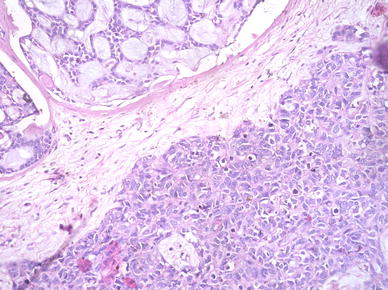

On surgical resection, the tumor was vascular, encasing the facial nerve and infiltrating the subcutaneous tissue and adjoining fat planes. On gross examination, the tumor measured 5 × 4 × 2 cm and replaced the entire parotid except for a thin wedge of grossly uninvolved tissue at one side. The cut surface of the tumor was variegated with solid, cystic, hemorrhagic and necrotic areas. On microscopic examination the tumor was primarily composed of sheets and nests of cells with intermediate to large-sized hyperchromatic nuclei, prominent nucleoli, scant eosinophilic cytoplasm and frequent mitosis (>20/10 hpf) (Fig. 2). The tumor nests were devoid of surrounding myoepithelial cells. Areas of necrosis (~10% of tumor area) and desmoplasia were seen. No intratumoral calcification was present. A discrete focus of conventional adenoid cystic carcinoma (grade II) occupying <10% area of the studied sections was identified. The tumor cells in this focus were arranged entirely in cribriform pattern showing small basaloid cells with interspersed pseudocystic spaces containing fuschinophilic acellular hyaline material and infrequent mitosis (~1/10 hpf; Fig. 3). Extensive perineural and lymphovascular invasion by tumor cells was seen. The tumor was diffusely infiltrating the adjoining salivary gland, fibrofatty tissue and skeletal muscle. A single lymph node was identified in the attached fat, metastatic deposits in which showed presence of high grade areas along with few foci of conventional ACC. A retrospective review of the fine needle aspirate smears revealed few small aggregates of isomorphic basaloid cells.

Fig. 3

Conventional ACC component with isomorphic basaloid cells in cribriform pattern (upper left) and high-grade undifferentiated ACC component (lower right)